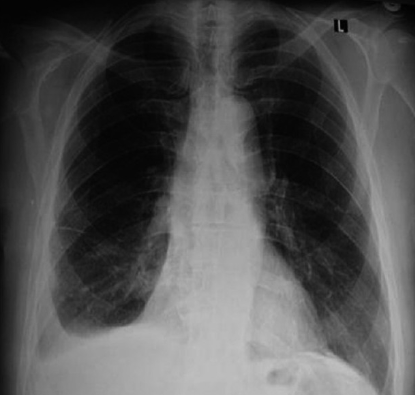

72세 남성이 우측 가슴 통증과 숨가쁨을 호소하며 병원에 도착했다. 환자의 흉부 X선 검사 결과는 아래와 같다. 이 환자에게 가장 먼저 시행해야 할 검사는 무엇인가?

우측 흉통과 호흡곤란으로 내원한 남성에서 시행한 X선 검사상 Rt. CPA blunting(사진이 잘 보이지는 않는다)이 보인다. pleural fluid를 확인하기 위해 lateral decubitus chest X-ray를 촬영할 수 있다.

최근에는 lateral decubitus를 촬영하기 보다는 흉부 초음파를 시행하여 흉수에 대한 진단과 천자를 시행한다.

In Harrison 21st (2197p): "Chest ultrasound has replaced the lateral decubitus X-ray in the evaluation of suspected pleural effusions and as guide to thoracentesis."